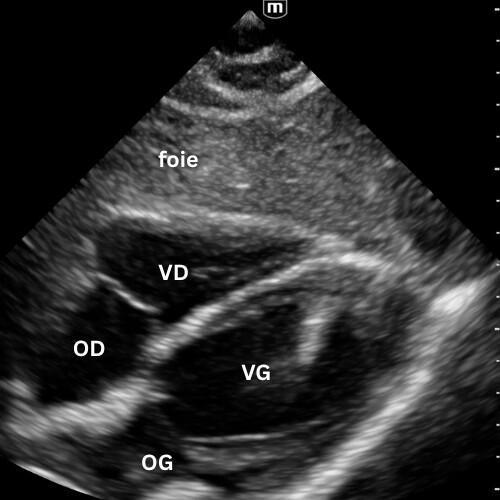

🔹 Vue Parasternale Grand Axe

→ Le cœur se contracte-t-il correctement ?

Sonde au 3ᵉ–4ᵉ espace intercostal gauche, bord sternal, marqueur vers l’épaule droite.

Montre le VG, le VD antérieur, l’oreillette gauche, la valve mitrale, la valve aortique et la racine de l’aorte.

On y évalue :

- la contractilité du VG ;

- la présence d’un épanchement péricardique postérieur ;

- l’aspect de la racine aortique (dilatée, disséquée, hyperéchogène) et la mesure de la chambre de chasse du VG.